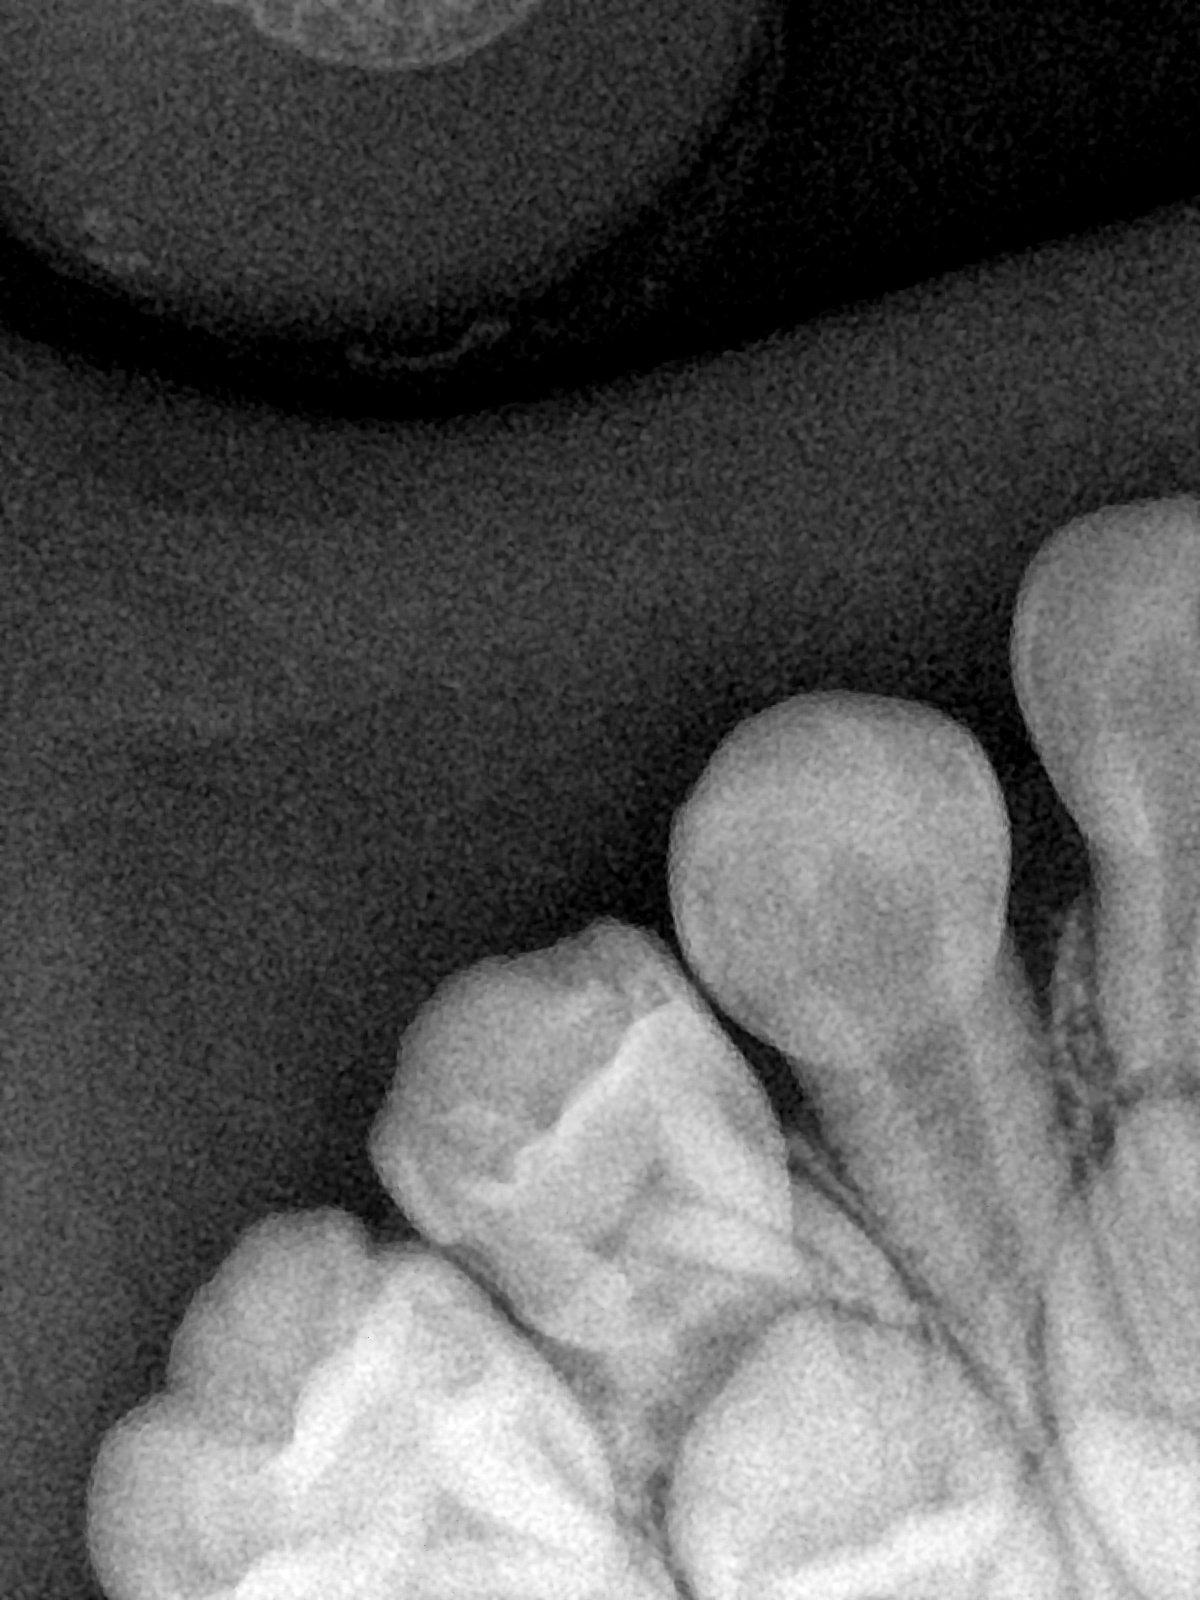

CR/DR 牙齿分割阶段记录

当前进展

- 完成了 CR/DR 牙齿相关分割训练

- 当前结果已经达到阶段预期,但仍有细节问题需要继续处理

相关测试

遇到的问题

- 训练过程中出现过 mask 下移问题

- 部分结果会出现 box 填充异常

- mask 边缘仍然有比较明显的锯齿感

参考

第二版算法问题测试